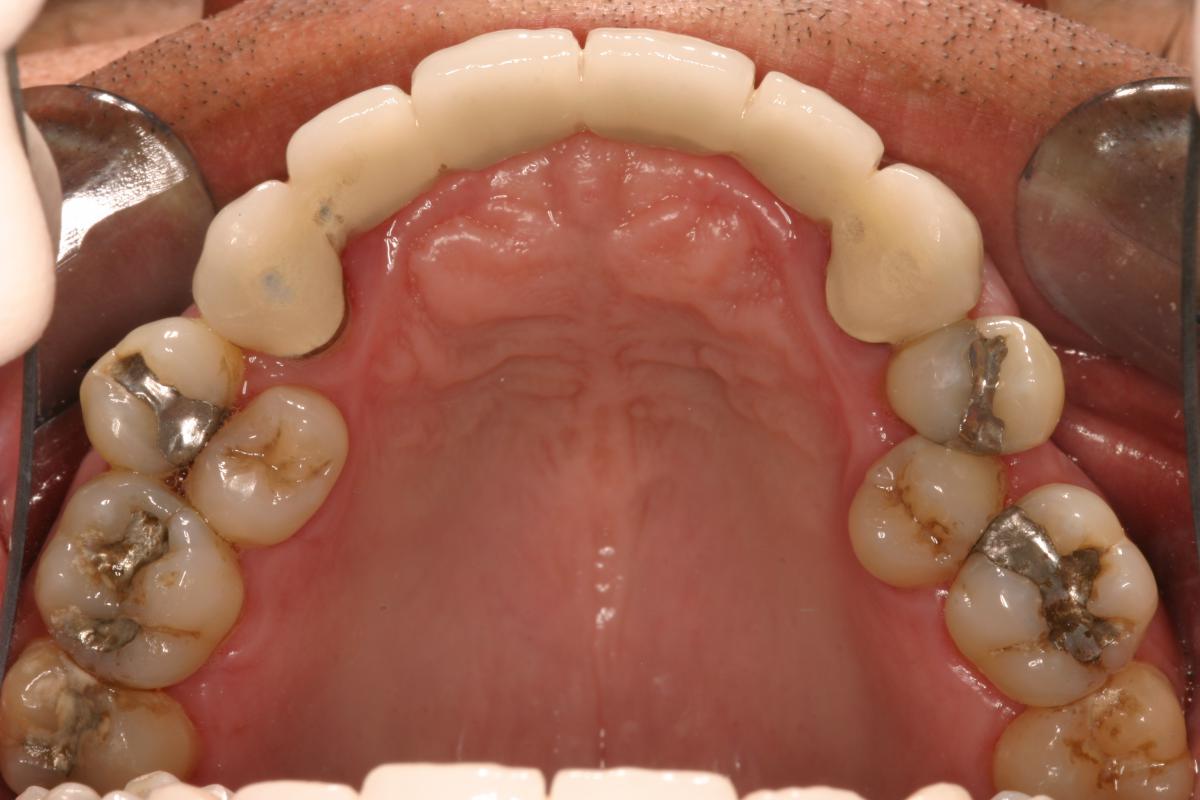

Full Mouth Restoration, also known as full mouth reconstruction or rehabilitation, is the process of rebuilding the teeth, bones and tissues located in both the upper and lower jaw. This procedure corrects problems with bite position, efficiently deals with the appearance of teeth and gums, and most importantly, tackles medical complications and solves the main source of the patient’s dental condition.

Crowns & Bridges are considered the most common dental restorative procedure in the field of dentistry. They are fixed dental prosthetic devices cemented on natural teeth or implants. A crown is a hallow cap made of porcelain or ceramic, gold and metal alloys, acrylic and ceramic. Bridges on the other hand is a fixed partial denture used to replace missing tooth by permanently anchoring an artificial tooth to adjacent natural tooth. Bridges are used to prevent gaps left by missing tooth that may cause the remaining teeth to shift into the empty space which could result to bad bite or gum disease.